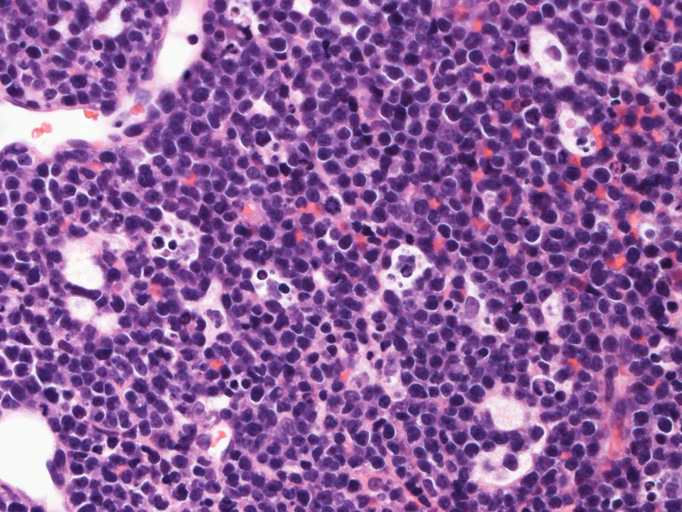

組織・細胞病理所見

エコーガイド下肝腫瘤針生検組織

尾状葉の腫瘍から16G, 11mm穿刺針で5mm, 2mmの組織を採取した。2mmの組織は線維組織と肝組織で腫瘍細胞を含んでいなかった。穿刺針洗浄液をkaryotypeに提出する。

liver biopsy x10liver biopsy x20生検組織スタンプ標本